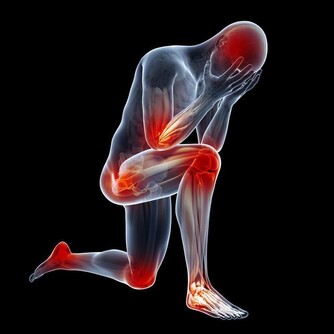

01.失眠、煩躁和腿抽筋

老是感覺身體沉重,做事無精打采的話,有可能體內缺乏維生素C、維生素D以及礦物質鐵、鉀、鎂,可適量吃點土豆、香蕉等富含鎂、鉀的食物。

9.手腳冰涼

輕微缺硒的人血液循環不好,會覺得手腳冰涼;

嚴重缺硒則導致免疫力低下、視力減退、易患心血管疾病和腫瘤。